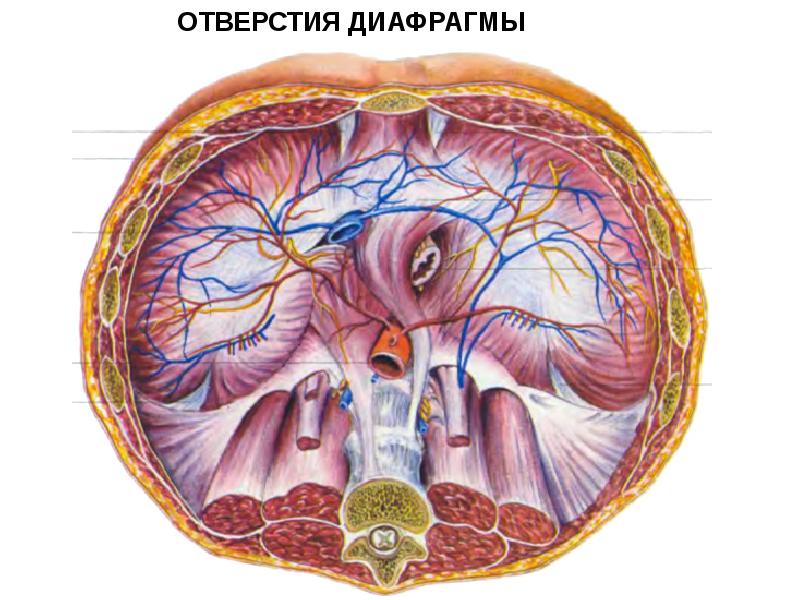

Анатомия диафрагмы и треугольника Бохдалека